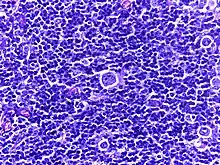

![]() | Diffuse B-cell lymphoma | Lymph node FNA specimen showing diffuse large B cell lymphoma. | Category: Histopathology of diffuse large B cell lymphoma | Diffuse large B-cell lymphoma |